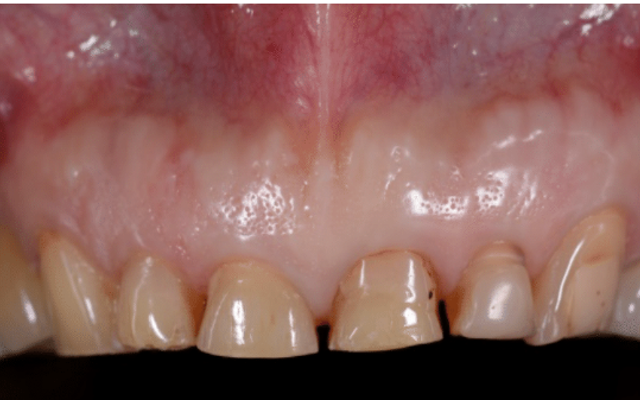

Crown lengthening can also be carried out for cosmetic reasons to expose more tooth structure to improve the appearance of the teeth or to reposition the gum tissues to an aesthetically acceptable position. This is a procedure that is often required where a patient has a “gummy smile” to reduce the amount of gum that is showing (Figure 9D, 9E and 9F).

Patient has worn their teeth down and has insufficent tooth structure for restoration with crowns.

Following crown lengthening, the gum has been repositioned to expose enough tooth structure for restoration with crowns.